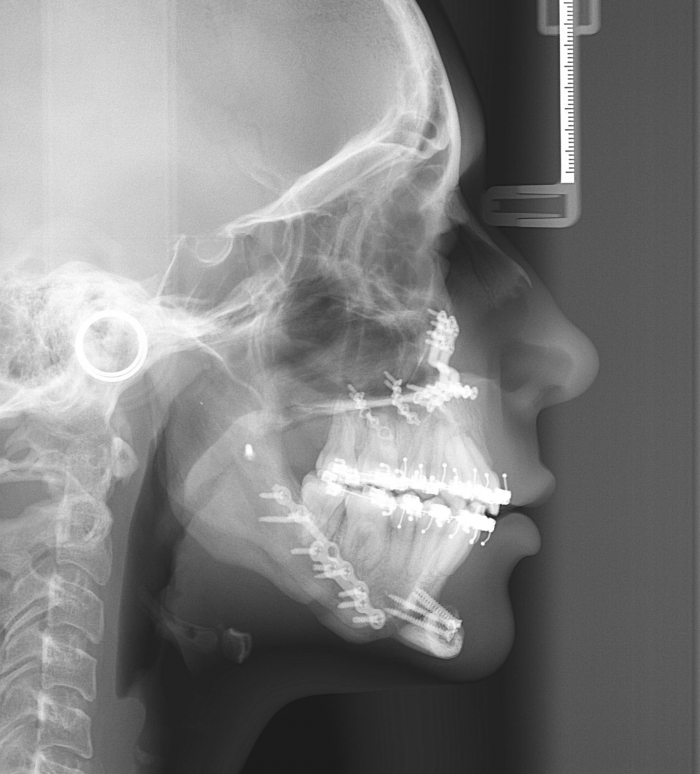

Telerradiografia inicial

Telerradiografia após a cirurgia 2018